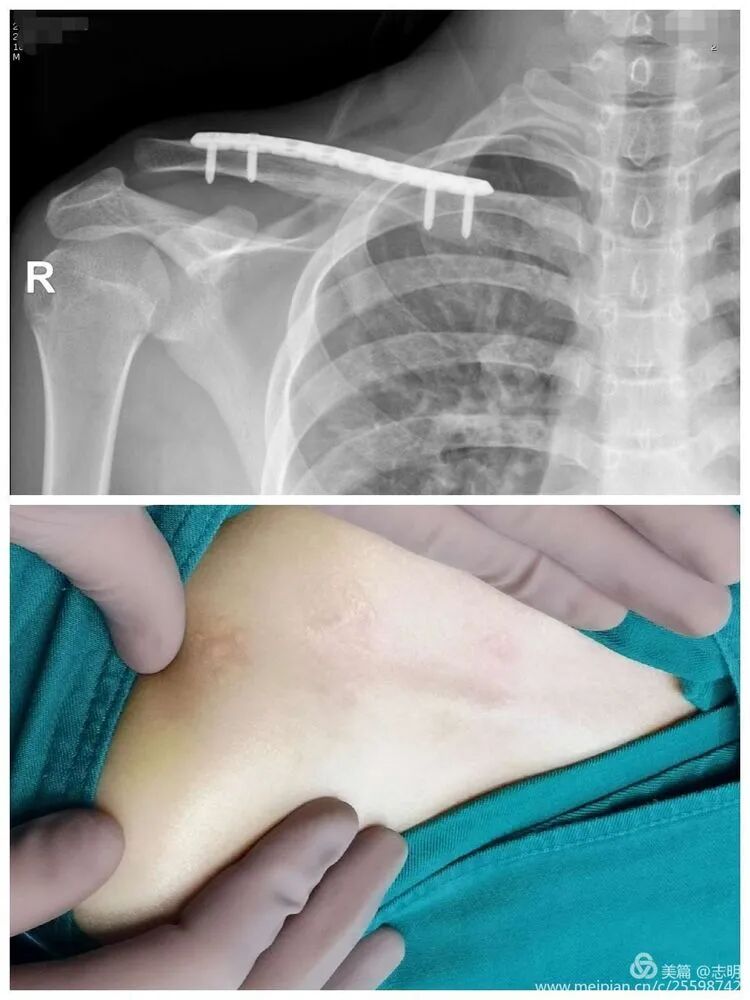

(This image shows a percutaneous tool, possibly for tunneling or reduction assistance).

(X-ray showing pre-reduction fracture).

(Example of pre-operative imaging, likely an X-ray showing fracture).

(Image showing patient preparation with clavicle marked and padding).

(Image showing the sterile draping including the arm).

(Image showing plate used for surface marking to define incision points).

(Clinical image showing surgeon's hands manipulating the shoulder, likely assisting in reduction).